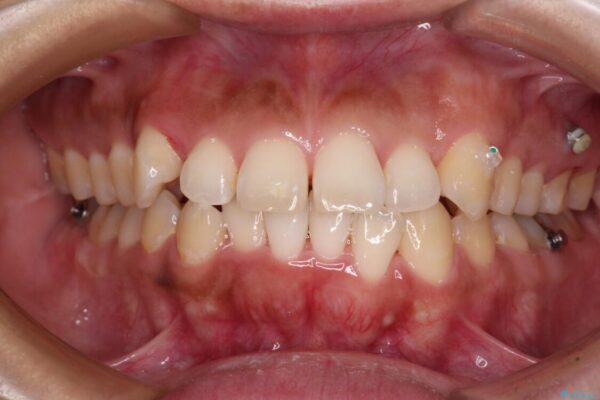

前歯の叢生と八重歯を気にして来院された患者様です。

治療前

• 【モニター】カリエール・ディスタライザーを併用した八重歯のインビザライン矯正 治療前画像